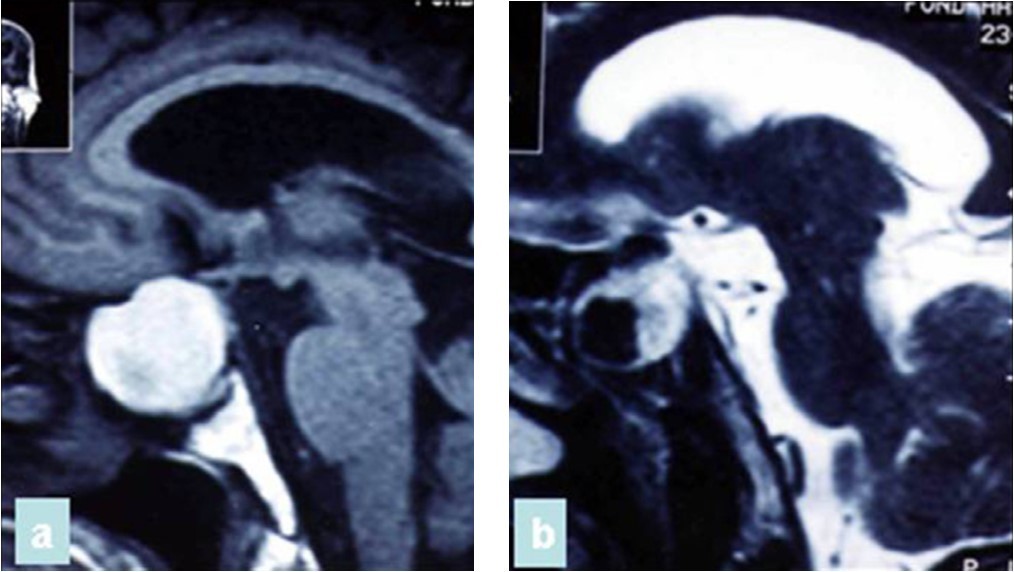

A 47 year old patient with no previous medical history presented with features of raised intracranial pressure, statokinetic cerebellar syndrome as well as left sided hemiparesis. The diagnosis of posterior fossa space occupying lesion was made. Neuroradiologic investigations demonstrated posterior fossa lesions. Magnetic resonance imaging and spectroscopy were in favor of a multiple infective process (Figure 1). Stereotatic biopsy was carried out on the patient and parasitological and histological examinations of the specimen concluded to a filamentous fungal infection of Aspergillus type. Culture and staining techniques categorized the specie as Aspergillus fumigatus (Figure 2).

Figure 1.cerebral MRI axial T1-weighted (A) and coronale (B), showing a multiples well circumscribed posterior fossa lesions

Patient was placed on intra veinous amphotéricin B but this was complicated with acute active hydrocephalus warranting external ventricular drainage (Figure 3). Subsequently, he developped staphylococcal meningitis as day 8 post op, treated with intra veinous vancomycin. Patient developed renal insufficiency and hyperosmolar non ketotic coma for an unknown diabetis for which amphotéricine B therapy was stopped. His neurological status deteriorated with a Glasgow coma scale (GCS)7/15. Posterior fossa surgery was performed with excision of the fungal abscess (Figure 4) and Voriconazol was instituded post operatively for fungal therapy with improvement of the neurological status to GCS 13/15. But the patient succumbed to acute cardiac failure.

Figure 3.cerebral CT scan with axial view showing acute hydrocephalus (A) and control after external ventricular drainage (B)

Figure 4.cerebral CT scan pre operative (A) and post operative (B) after posterior fossa surgery with total removal or abscesses